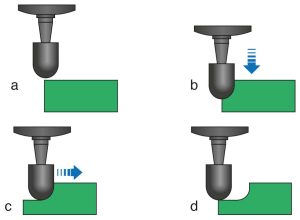

The occlusal rest seat can be prepared with rond burs, round-tipped or progressively narrower diamond burs (Fig. 10-34). When using a round diamond bur, care must be taken not to create an undercut in the rest seat (Figure 10-35). Round-tipped and progressively narrower burs allow for preparation without creating an undercut (Fig. 10-36).

a) Tapered bur positioned above the enamel surface

b) Bur advanced in the vertical direction

c) Bur advanced in a horizontal direction

d) No undercut formation when the bur is removed